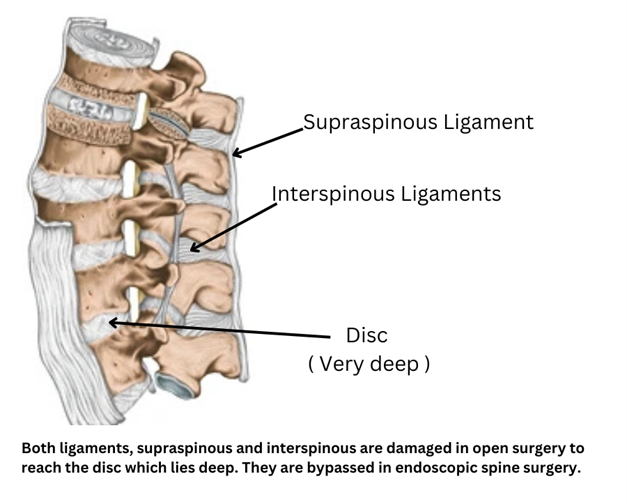

Ligaments are tight structures that don’t allow movement beyond physiological range between two bones.Two ligaments, supraspinous ligaments and interspinous ligaments get damaged in open spine surgery tampering the stability of spine.